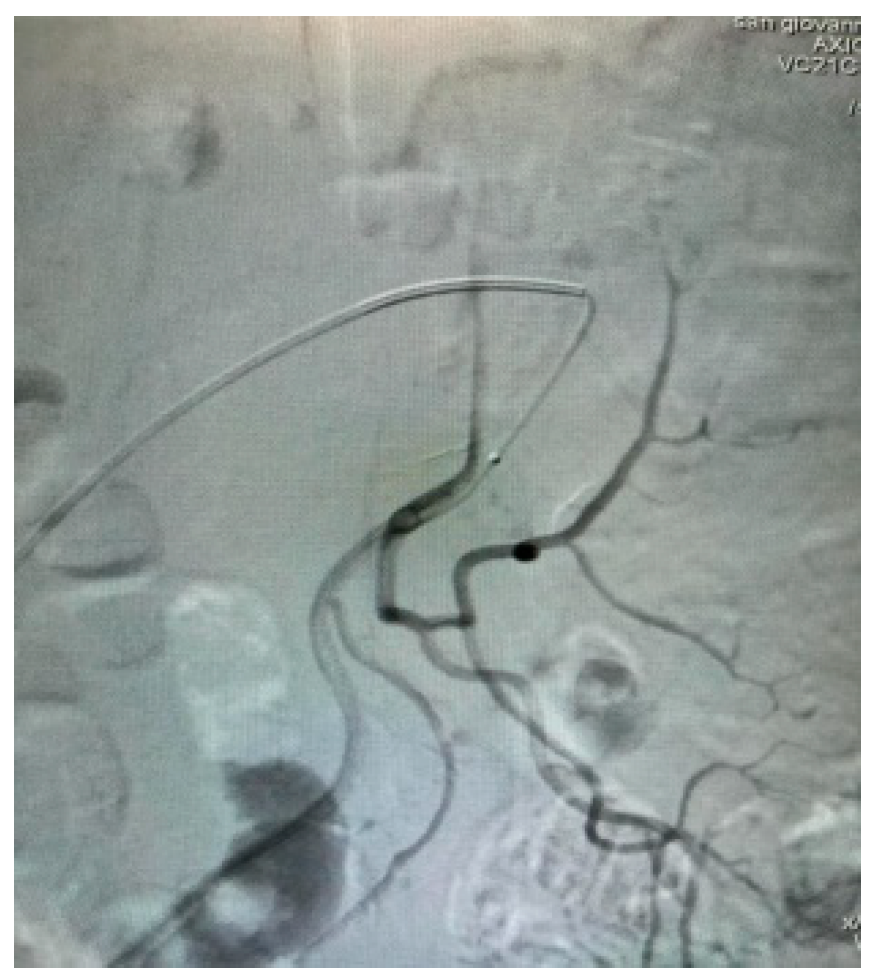

Appendix A.2. Clinical Case 2: Treatment of Endoleak Type II Inferior Mesenteric Artery